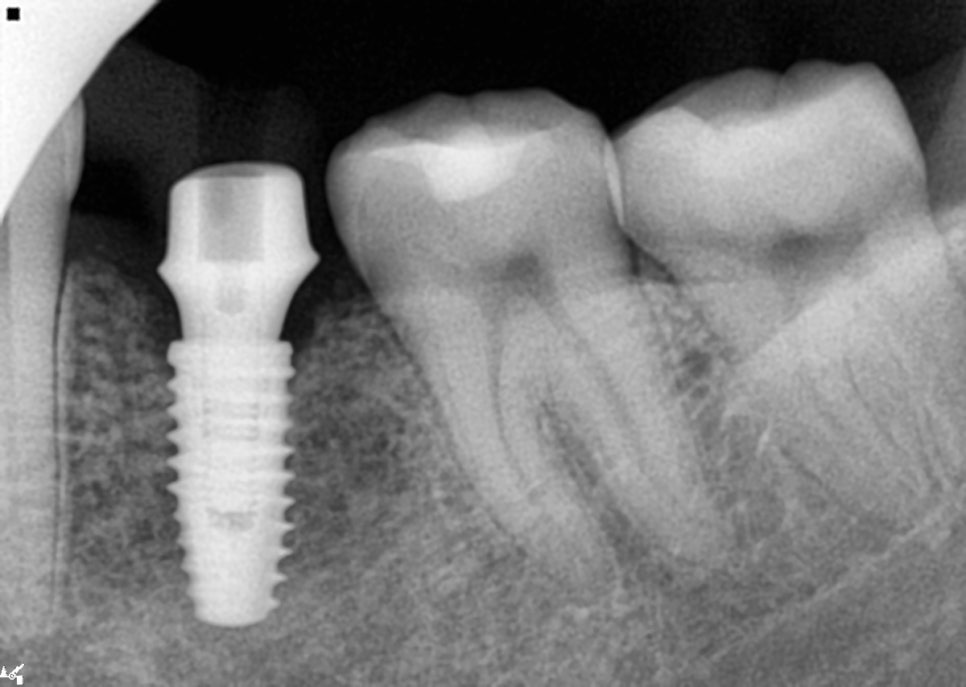

아래쪽 임플란트

아래쪽 어버트먼트 장착

위쪽 3개 어버트먼트 장착 완료

어버트먼트는 장착 후에는 반드시

방사선 사진으로 체결 상태를

더블체크 해야합니다.

눈으로 잘 된것처럼 보이지만

그렇지 않을 수 있기때문에

꼼꼼하게 확인을 해야하기 때문이죠.